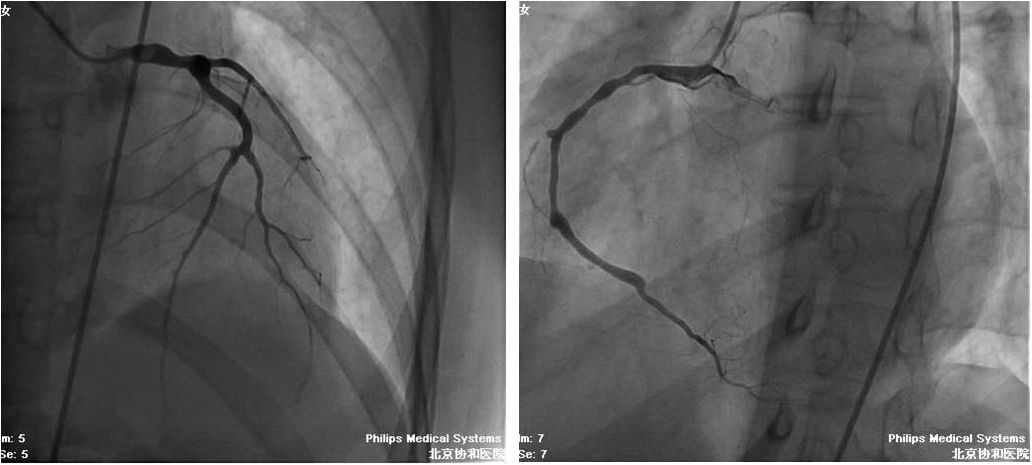

女,15岁

双下肢红斑1年,全身乏力1月,喘憋咯血2周

BP:(左上肢)161/114mmHg,(右上肢)140/?mmHg,下肢血压测不出

NT-Pro-BNP 12653pg/ml

右侧肱动脉近心段局限性重度狭窄,

双侧股总、股浅动脉狭窄

治疗前

胸闷明显好转、无咯血,可以平卧,平地活动不受限

2个月后